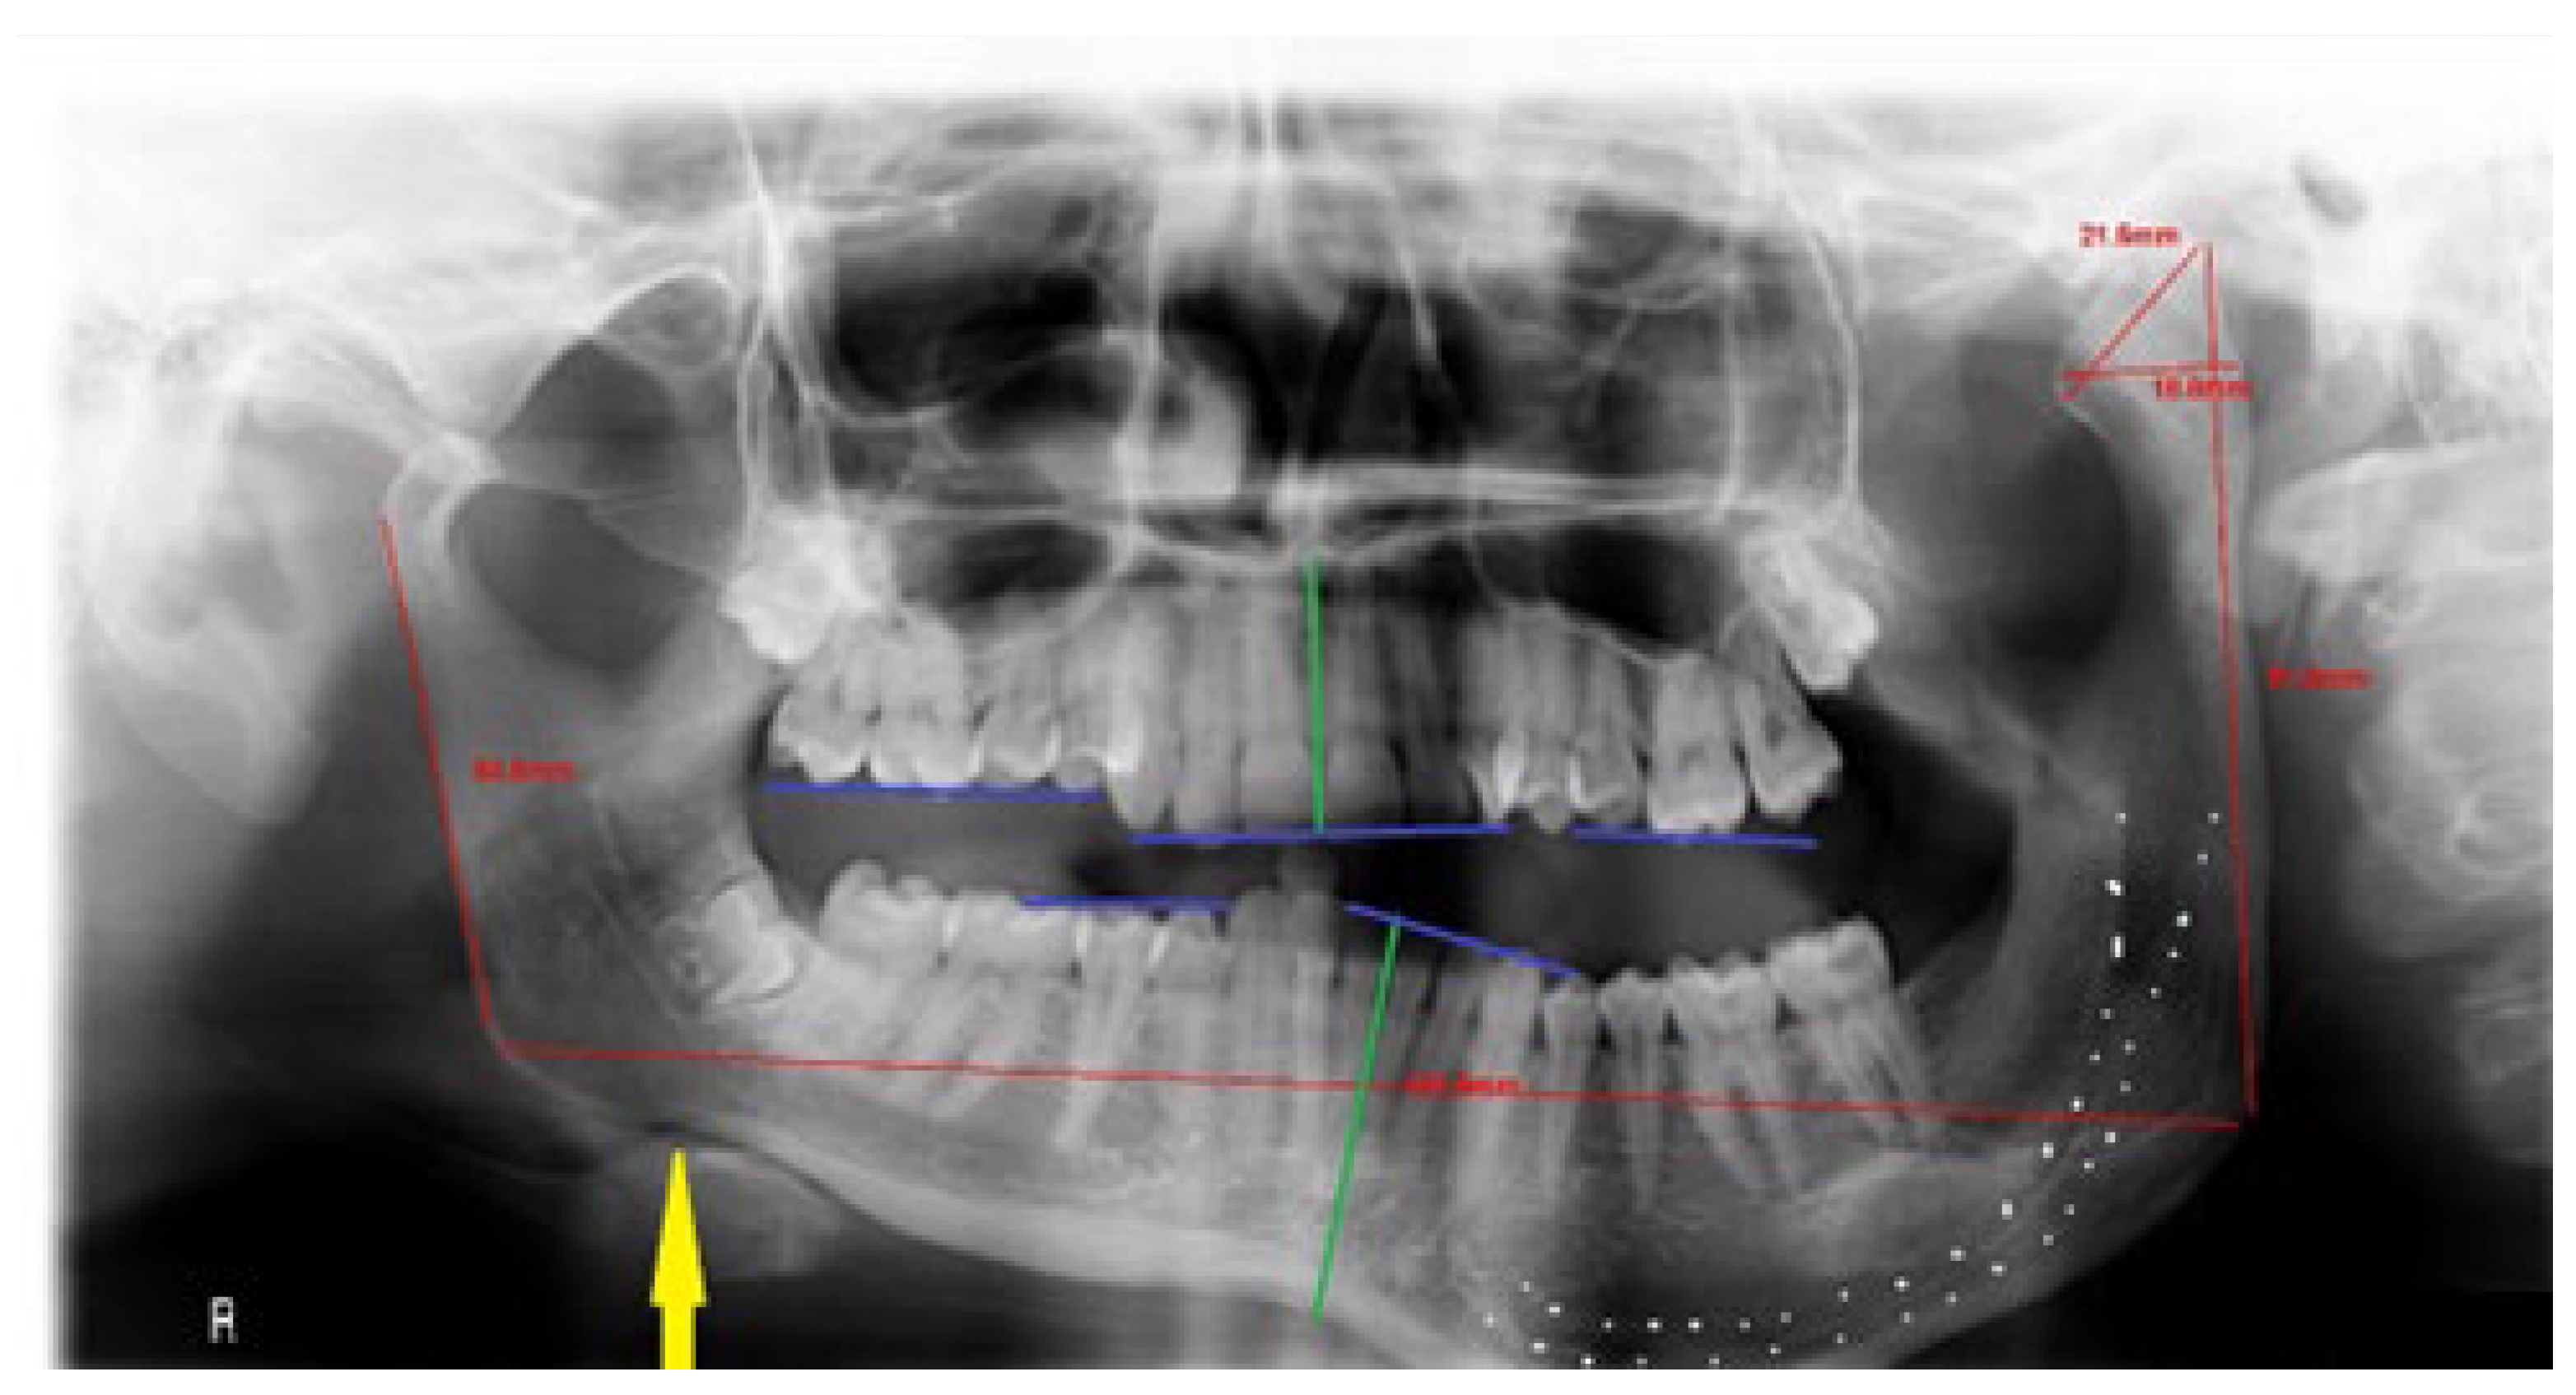

G—gonial angle, presence of antegonial notch (Figure 1)—present on the contralateral side from the bone overgrowth in the mandible angle, manifested as angle curvature, rather than a smooth oval angle in the affected overgrowth side;

Figure 1. Presence of an antegonial notch on the healthy side (pointed with red arrow).